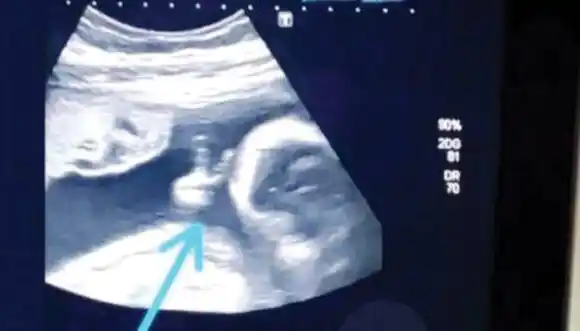

Todo lo que se sabe hasta el momento sobre la adolescente que se presentó en el hospital solicitando ver a �Ssu bebé⬝